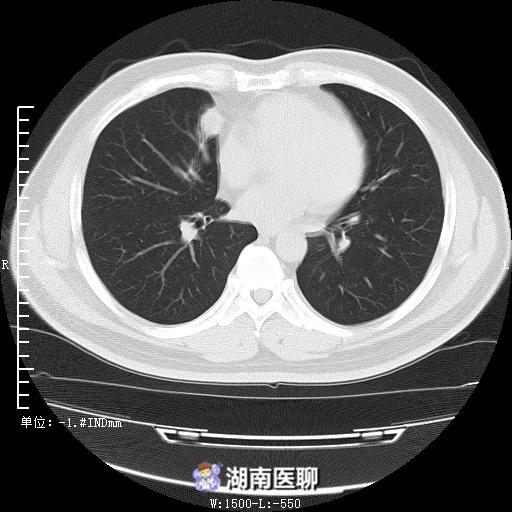

经过我们肺灌洗、抗感染等综合治疗,患者胸痛、呼吸困难症状逐渐缓解并治愈出院。

(出院时肺部CT)